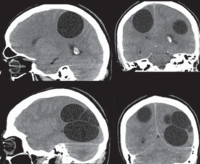

• Солитарная форма характеризуется наличием одиночной кисты. Образование часто достигает значительных размеров - до 60 мм в диаметре. В клинической картине превалируют фокальные эпиприступы и очаговые симптомы. Возможно радикальное хирургическое удаление. Имеет относительно благоприятный прогноз.

• Рацимозная форма отличается формированием гроздевидного конгломерата пузырей и многоочаговостью поражения. Встречается редко. В клинике преобладают тяжелые общемозговые проявления. Хирургическое лечение затруднительно.

• Томографические исследования. Позволяют выявить внутримозговое образование с тонкими стенками, определить его локализацию и объем. КТ головного мозга более информативно в отношении кальциноза капсулы, МРТ головного мозга лучше визуализирует стенки кисты.